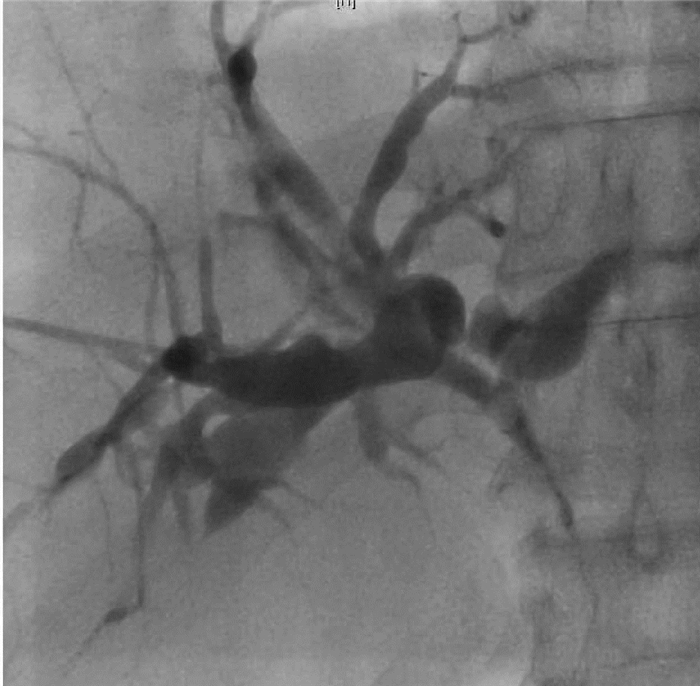

Viridans streptococci sepsis with liver abscess and hepatic vein thrombosis: A case report

Lina FENG, Yao WANG, Bo MA, Jianjie HUANG, Xiaoxue ZHANG, Xiaoyu WEN, Junqi NIU, Qinglong JIN

2021, 37(2): 405-407. DOI: 10.3969/j.issn.1001-5256.2021.02.032

Abstract(949) HTML (420) PDF (2002KB)(48)

Abstract: